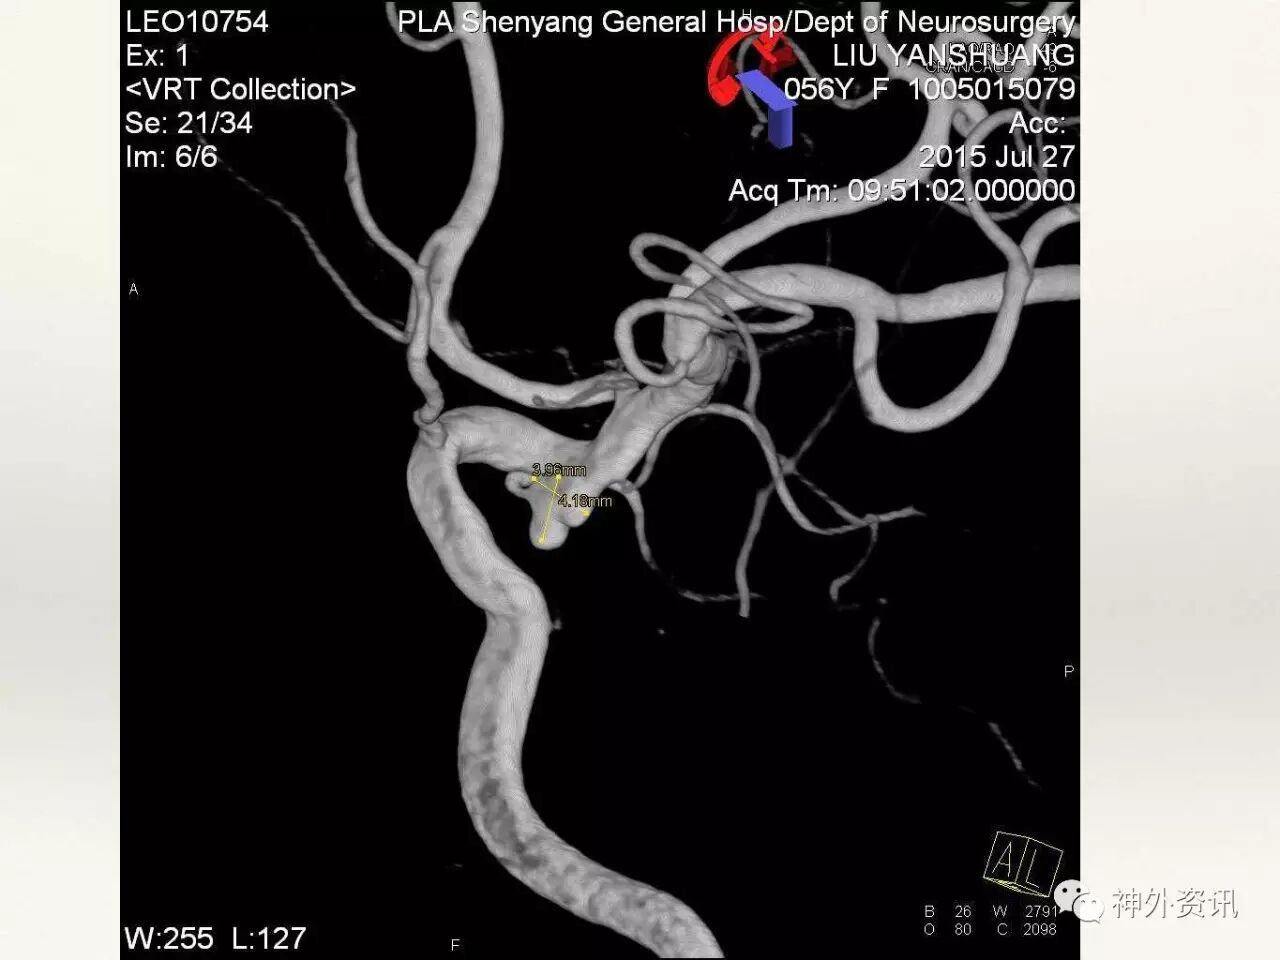

在东北地区率先开展了颈内动脉、大脑中动脉及基底动脉闭塞血管内再通、颅内动脉栓塞急性期取栓、血流导向装置治疗大型宽颈动脉瘤等,对颅内动脉瘤、动静脉畸形、颈动脉及颅内动脉狭窄、颈内动脉海绵窦瘘、硬脑膜动静脉瘘等外科治疗具有较深的造诣。完成脑血管造影8600余例,各类脑血管病介入手术共4500余例,动脉瘤、动静脉畸形、脑肿瘤、脑出血及脑外伤等外科手术1500余例。